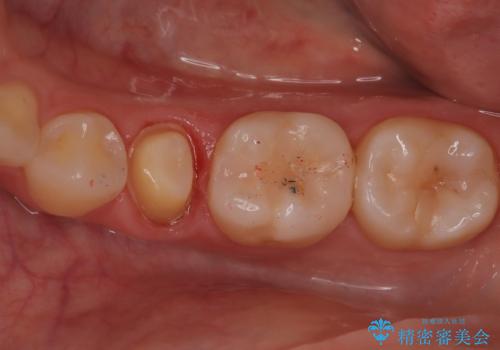

【オールセラミッククラウン】根管治療した歯の被せ物治療

- 根管治療した歯の被せ物の治療を希望され来院されました。

被せ物を行うことで、破折リスクを低下させることができます。

オールセラミッククラウン(スタンダード)で製作しています